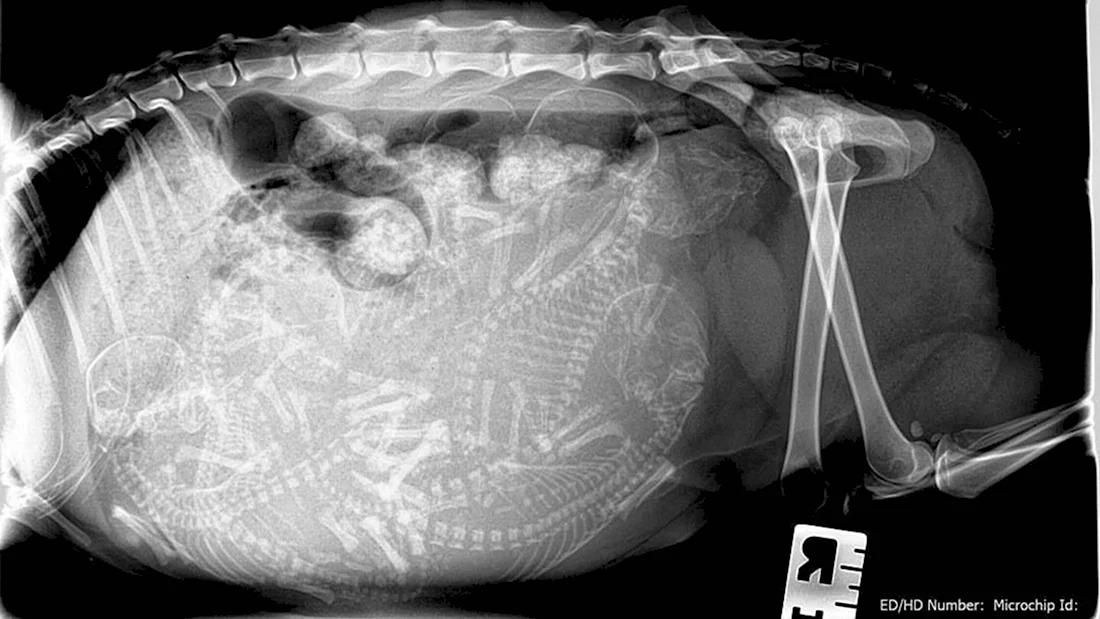

Погрузитесь в волшебный мир развития эмбриона кошки с помощью этой захватывающей галереи фотографий! Вас ждут 39 потрясающих фото и картинок, которые позволят вам увидеть каждый этап развития эмбриона. Эта подборка фотографий сразу привлечет ваше внимание и заставит задуматься о том, насколько удивительным может быть природа. Порадуйте свои глаза этой удивительной коллекцией фотографий и узнайте больше об удивительной жизни эмбрионов кошек!